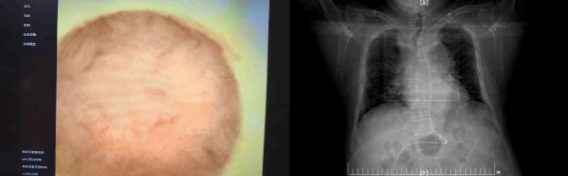

此次我院引进的床旁便携式可视化引导下鼻肠管置入技术,核心优势在于置管全程可视化。操作者通过高清内窥镜,可实时清晰观察食管、胃、十二指肠的解剖结构,如同为置管操作装上“透视眼”,精准把控导管走向,一次性将鼻肠管送达十二指肠或空肠的目标位置。相较于传统盲插法,该技术有效降低鼻腔黏膜损伤、导管异位等并发症发生率,提升操作效率,缩短置管时间,减轻患者不适感;无需依赖X线定位,既规避了辐射暴露风险,也减少了危重患者转运过程中的安全隐患,真正实现了精准、快速、安全、舒适的置管目标。